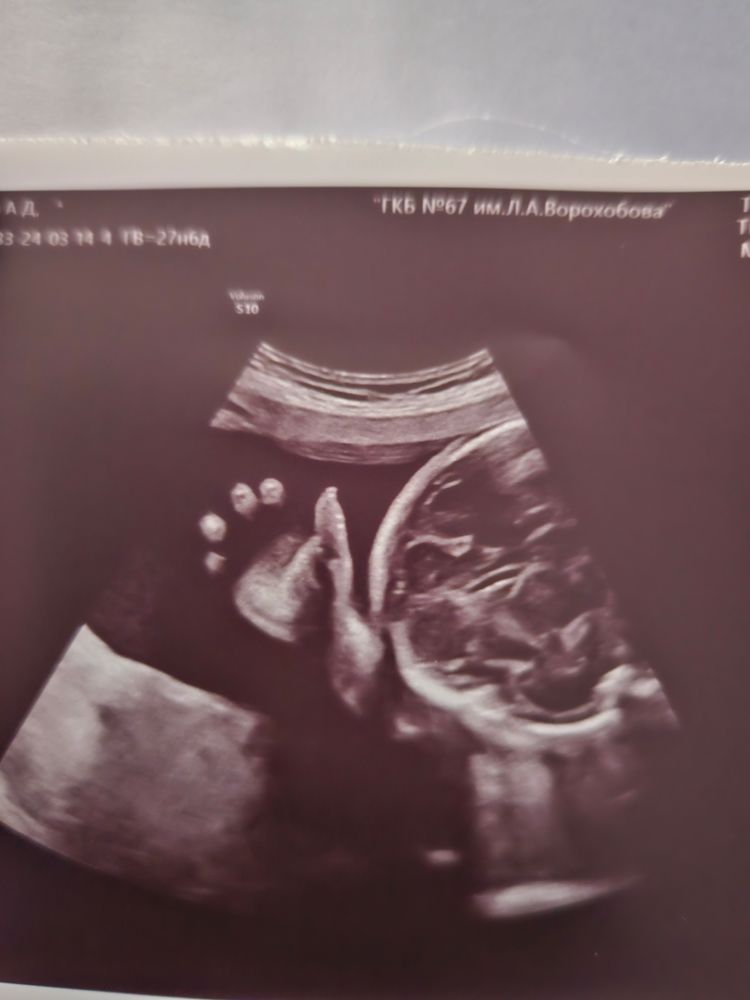

Итак, нам нам уже 28 неделек. Да, мы выступили в 3 триместр. А мальчик наш обогатырился аж до 1500гр, что соответствует 31 недельке. Да и ВДМ 31 см соответствует 31 недельке. Растёт не по дням, а по часам наш крепыш! 💪

Пинается, брыкается, копошится, ведёт активный образ жизни. Особенно если я вдруг легла и расслабилась. Как будто тычет и проверят жива ли я там вообще 😅 когда я активна и много шевелюсь, он спит и не тревожит.

Вообщем, у нас всё отлично. Работаем, растём, по выходным ездим в баньку. Мы бодрый и веселы 🥳 Тёмка машет всем ручкой